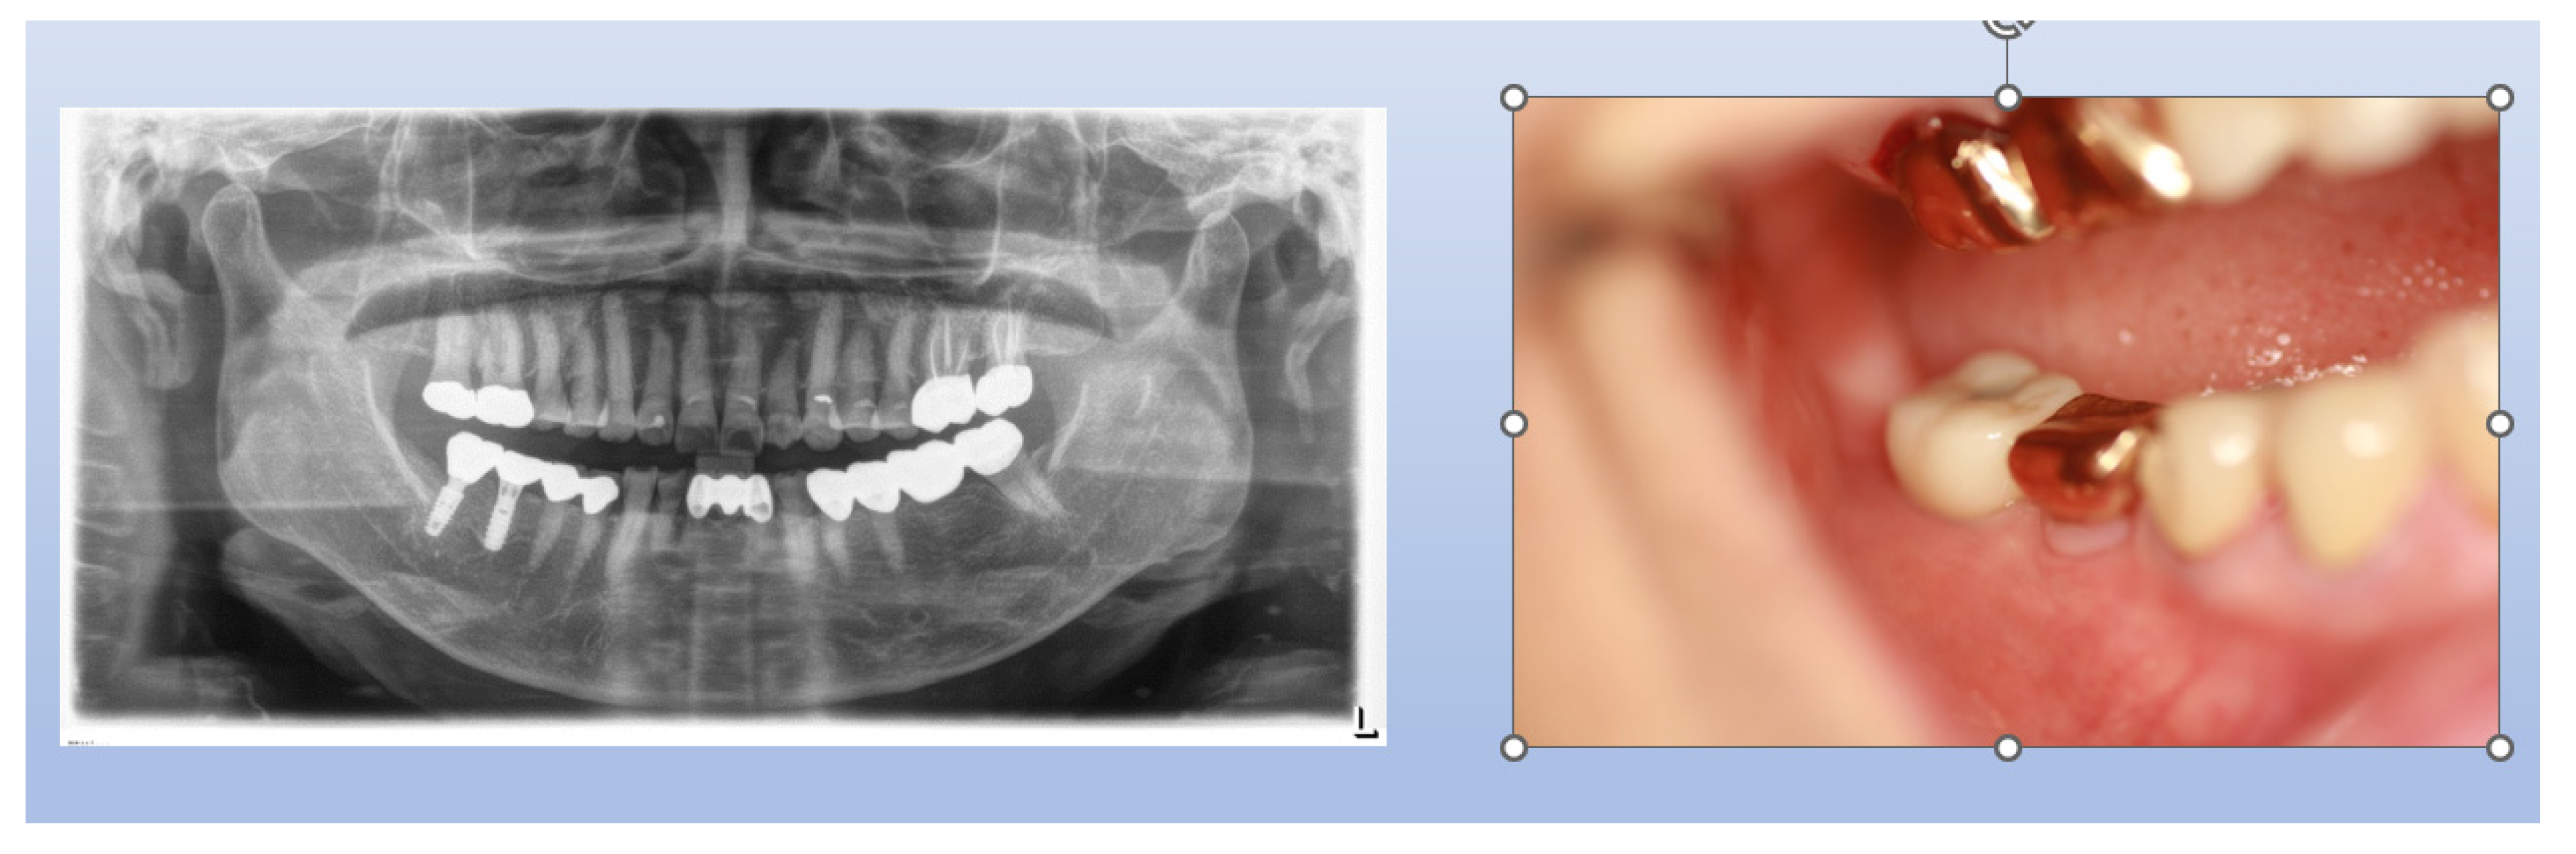

Figure 9. X-Ray Sequence of Healing Abutment Changes. This series of X-rays illustrates the procedural sequences for implant placement and subsequent adjustments. Initially, healing abutments measuring 5 mm in diameter and 2.5 mm in height were placed and covered with primary flap closure. After three months, a second operation was undertaken for the prosthetic procedure. During this stage, the sites were uncovered and longer healing abutments, maintaining the same profile as the initially embedded abutments, were connected to prepare for final prosthesis installation.

Figure 16. Transmucosal Soft Tissue Structures in Subcrestally Placed Implants. This figure presents clinical images showcasing the transmucosal area related to the junctional epithelium and connective tissue (the biologic width) in subcrestally placed implants (SPIs), captured either after the removal or before the placement of the prosthetic parts. Compared to epi- or equi-crestal implant placements, these SPIs exhibit a larger area of transmucosal soft tissue. The right image distinctly identifies three layers: the subcrestal zone, the Transitional Zone (TZ), and the marginal zone, where the pale pink color closely matches the adjacent oral epithelium.